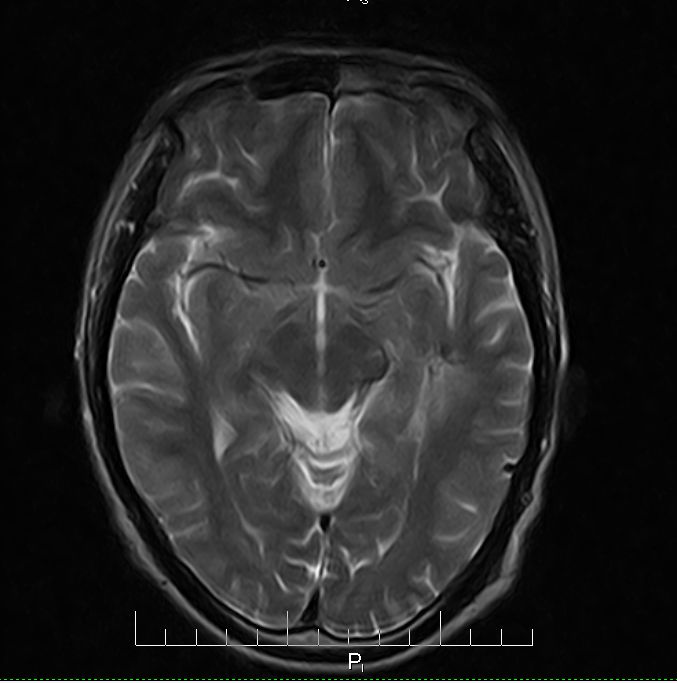

标题: MRI2379:30岁,男,癫痫10年,请各位看一下;CT示:左颞叶钙 [打印本页]

标题: MRI2379:30岁,男,癫痫10年,请各位看一下;CT示:左颞叶钙

左颞叶区见不规则点状混杂信号影

考虑血管畸形

支持2楼 左颞叶区见不规则点状混杂信号影,考虑动静脉畸形。

考虑左侧颞叶脑血管畸形(avm)。----t1低等高混杂信号,t2等高信号周边较多流空血管影[冠状位明显],mra左侧大脑中动脉受压,远侧聚集.

考虑avm,建议行增强扫描,看供血a与引流v,以明确诊断。